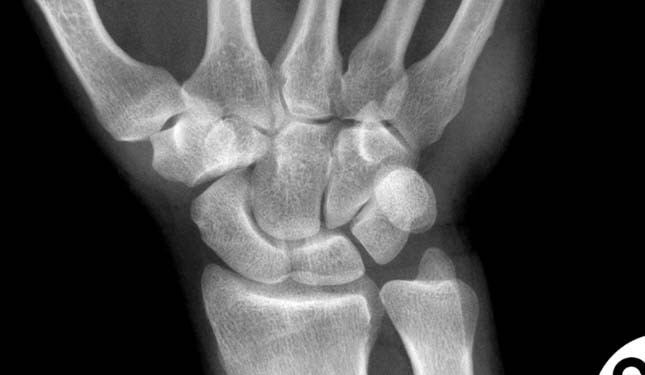

metakarpal kemik kırığı

2. metakarpal kemik fraktürü

2. metakarpal kemik bazis kırığı